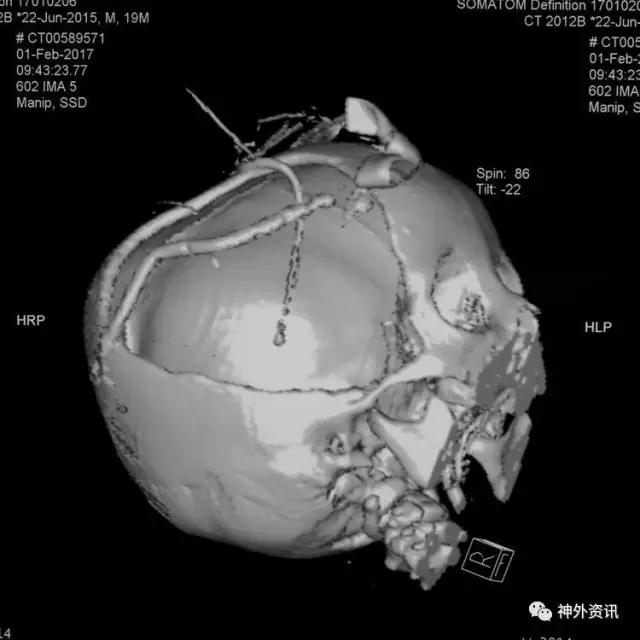

急诊在全麻下行右额颞顶开颅去骨瓣减压+脑室外引流+ICP探头置入术:

顶部小切口钻孔释放硬膜下血肿初步减压,取下骨瓣后硬膜张力高,其下可见硬膜下血肿:

咬除骨质至颧弓水平,超声引导右侧脑室穿刺引流: